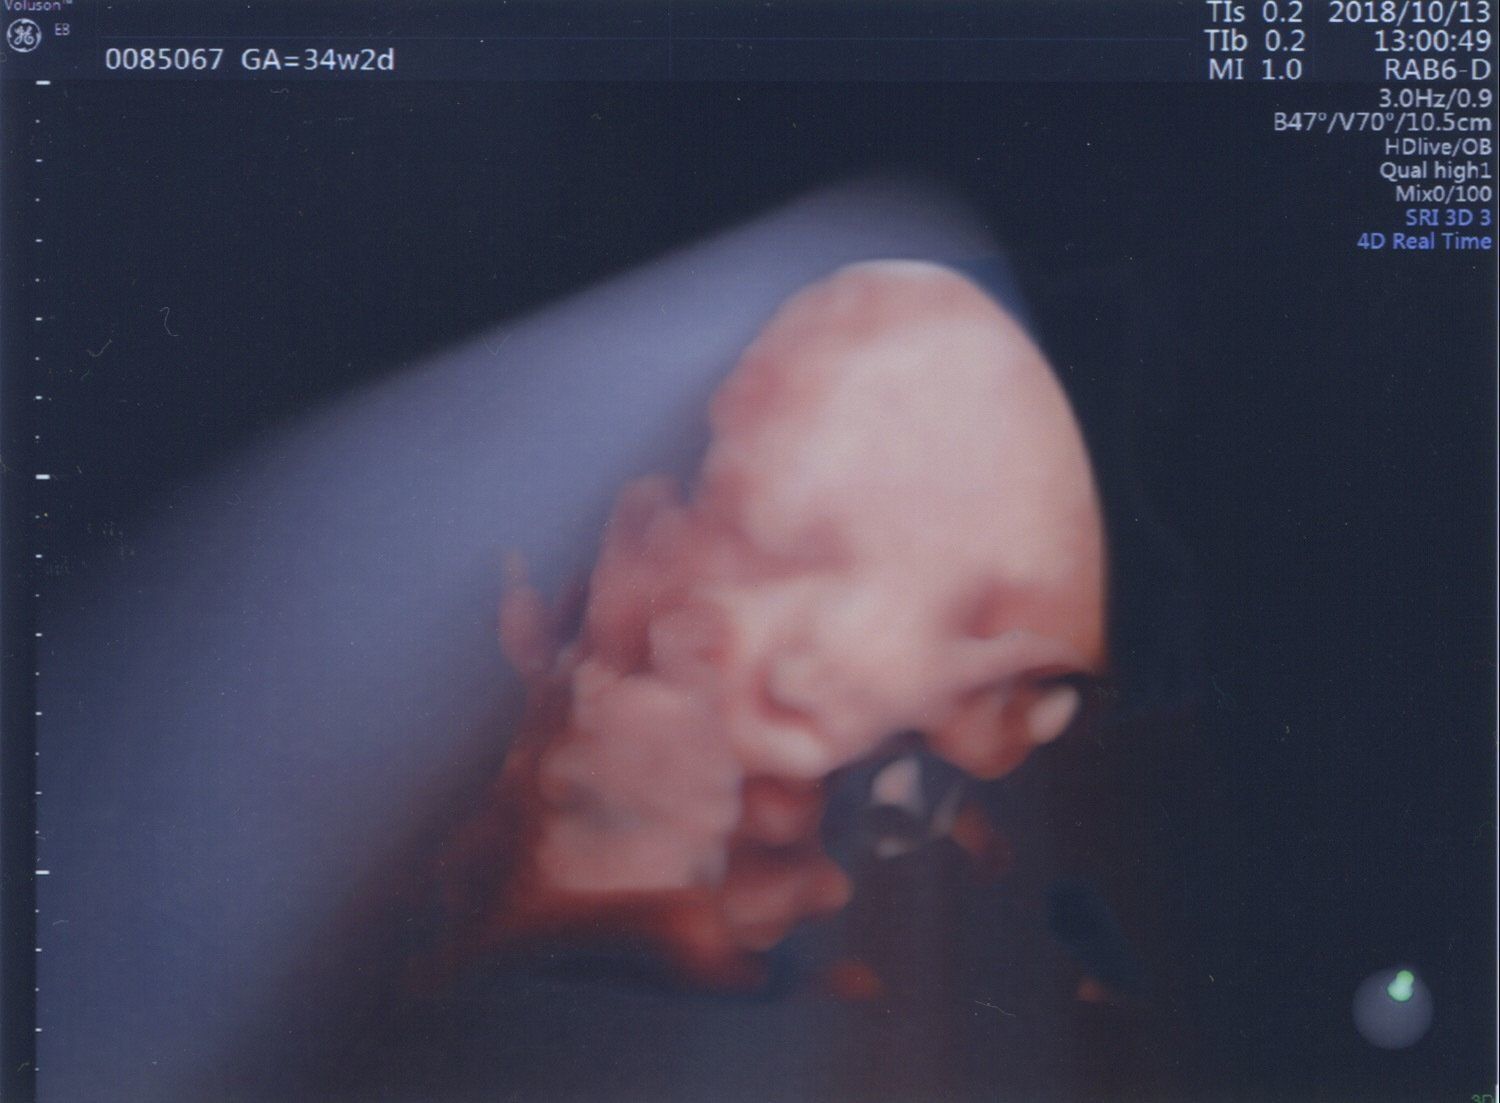

妊娠34週目 どっちに似てる?

妊娠34週目。この頃はいろいろな表情や動きを見せてくれるようになり、エコーを見るのが楽しみでした。よく手を頬や口元に当てているのは、生まれた今も変わりません。

顔立ちも良くわかるようになり、「口はパパ似だね」、「輪郭はママかな? 」なんて会話をしていました。